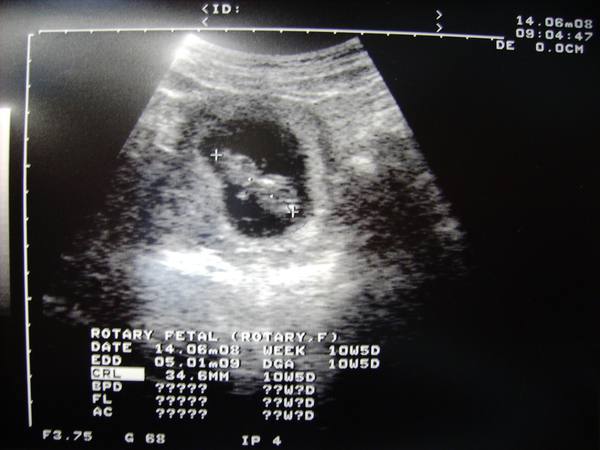

漂亮小鹿與周小熊的第10週(6/3-6/9)

周小熊:

頭頂到臀部的長度約3.1到4.2公分,體重約5公克

已有眼皮(保持緊閉),身体及器官、系統的發育大致已有雛形

大小約等於一個小西洋梨

周小熊先生,書上說,10週過後就已經安然度過寶寶最重要的發育期,

可是,今天小鹿媽媽說有一點點....所以我幫媽媽提前掛婦幼醫院的號

沒事沒事,平安無事,明天早上請你給爸媽這個禮物吧。

希望你健健康康平平安安的長大喔,拜託拜託。